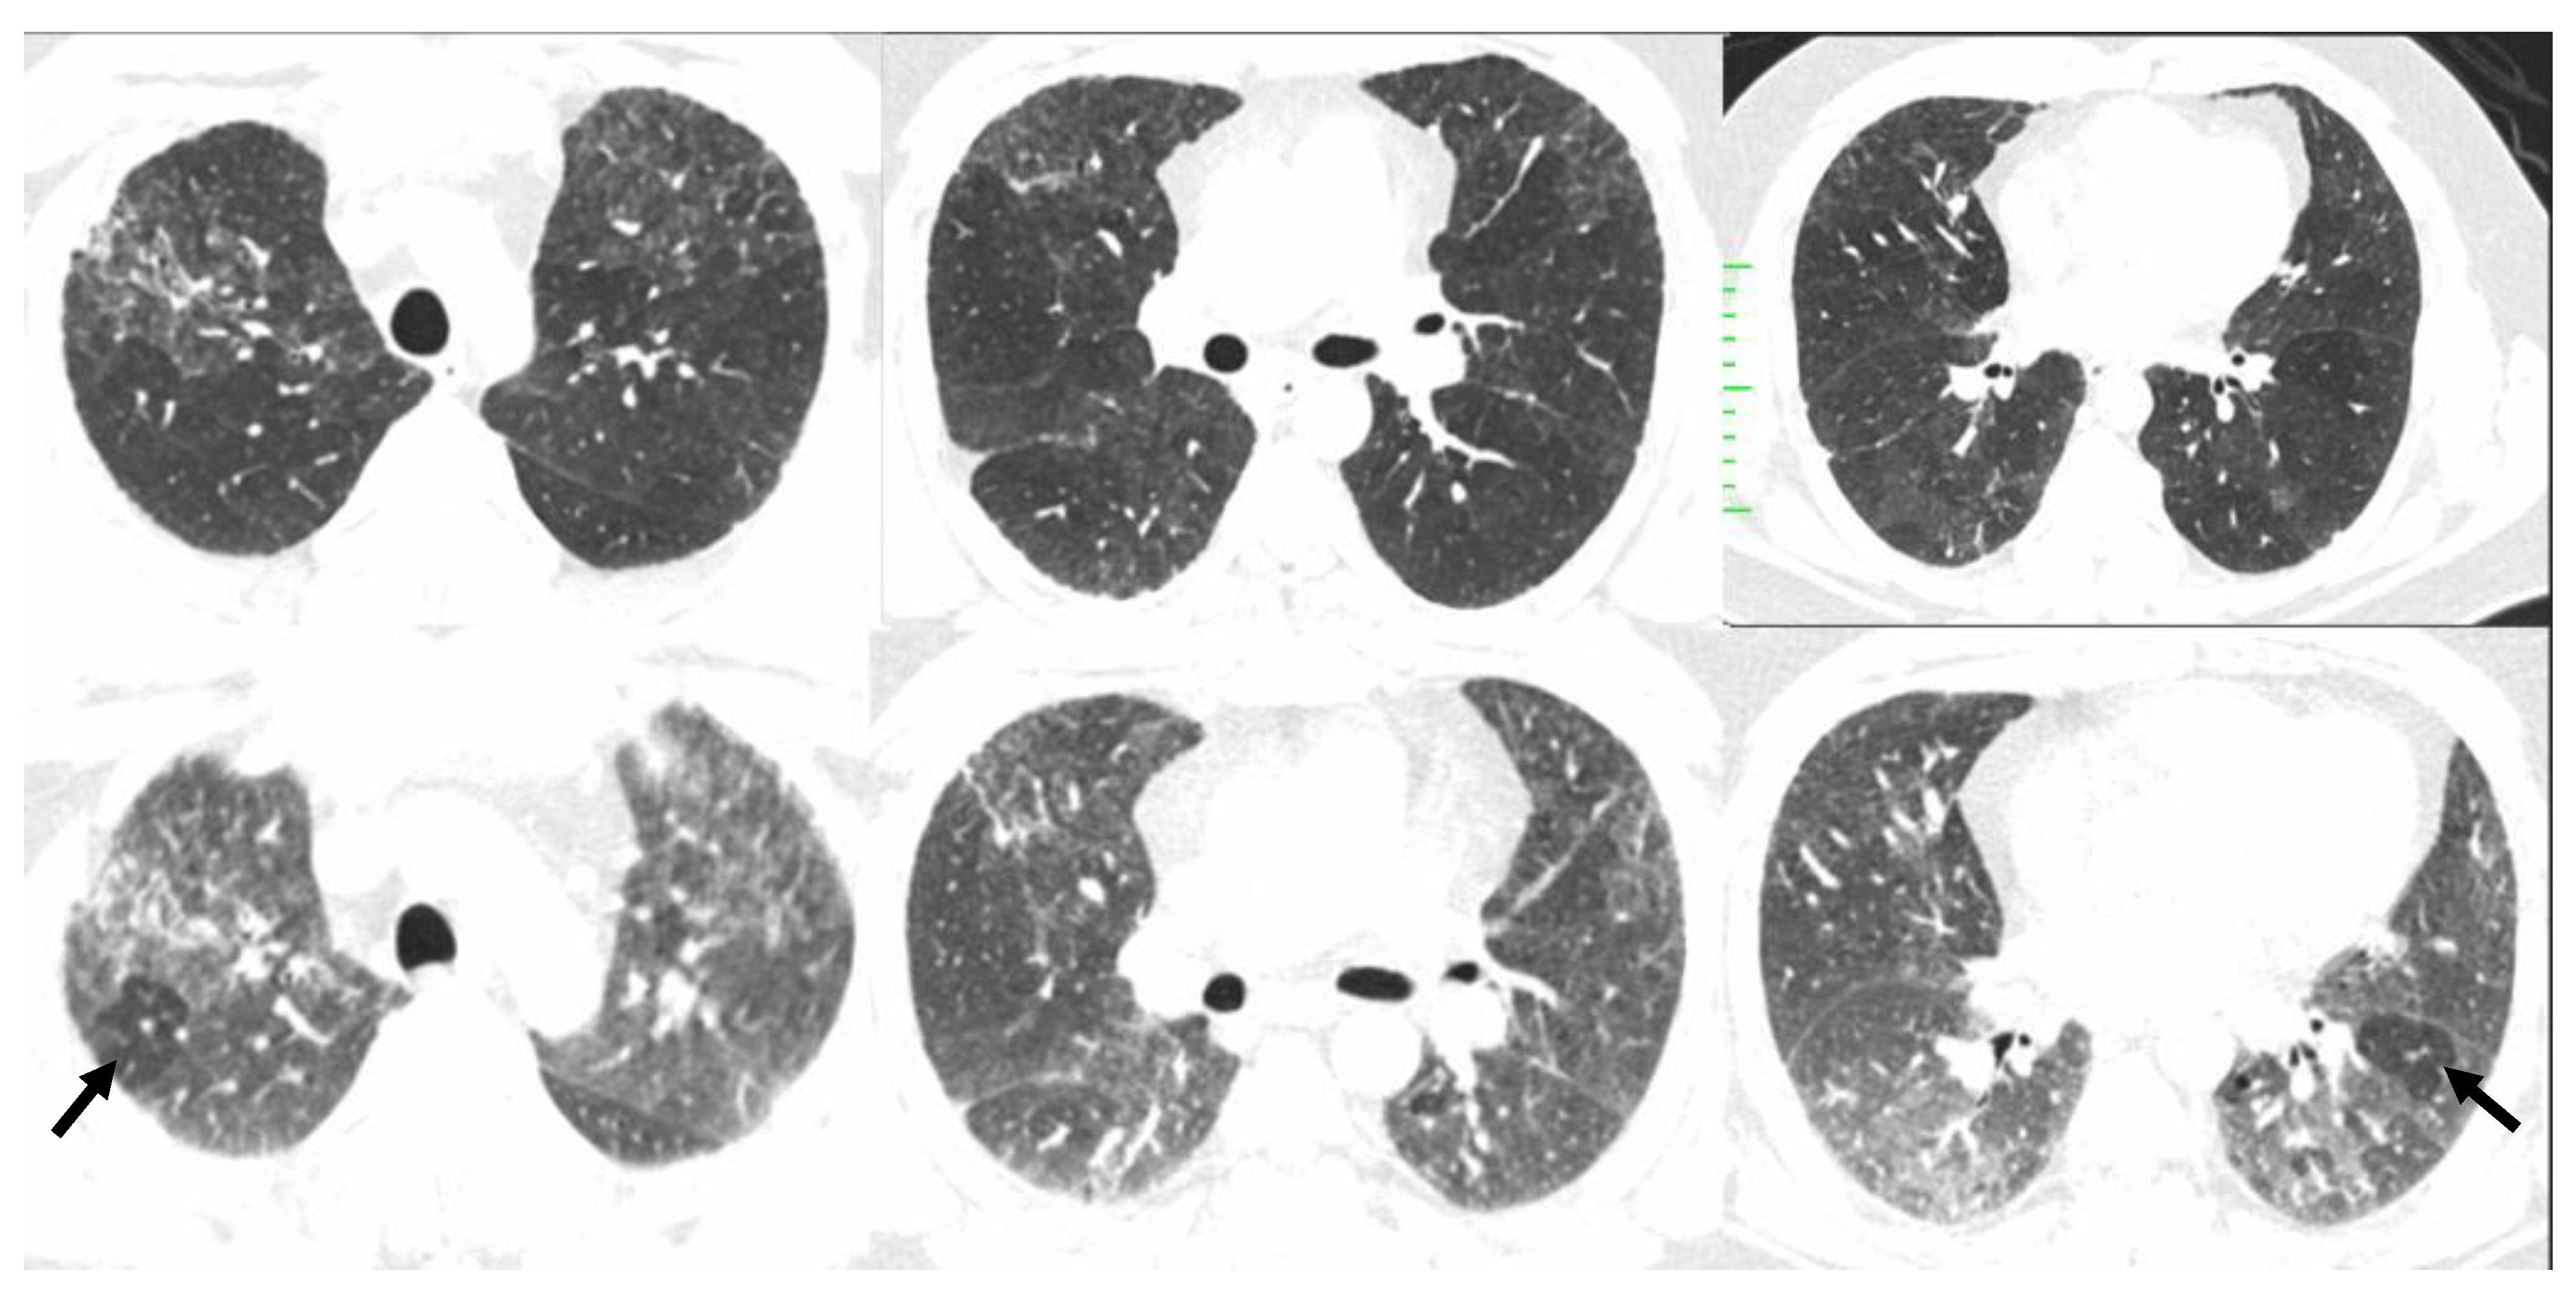

| Typical HP Pattern (Suggests a Diagnosis of HP) | Compatible with HP | Indeterminate for HP |

|---|---|---|

| At least one finding indicative of small airway disease | Not applicable | |

| Air trapping | ||

| Ill-defined <5 mm centrilobular nodules | ||

| At least one finding indicative of parenchymal infiltration | ||

| Mosaic attenuation | Diffuse and subtle GGO | |

| GGOs | Airspace consolidation | |

| Lung cysts | ||

| Distribution of findings | ||

| Craniocaudal: diffuse +/− basal sparing | Craniocaudal: diffuse (variant: lower lobe predominance) | |

| Axial: diffuse | Axial: diffuse (variant: peribronchovascular) | |